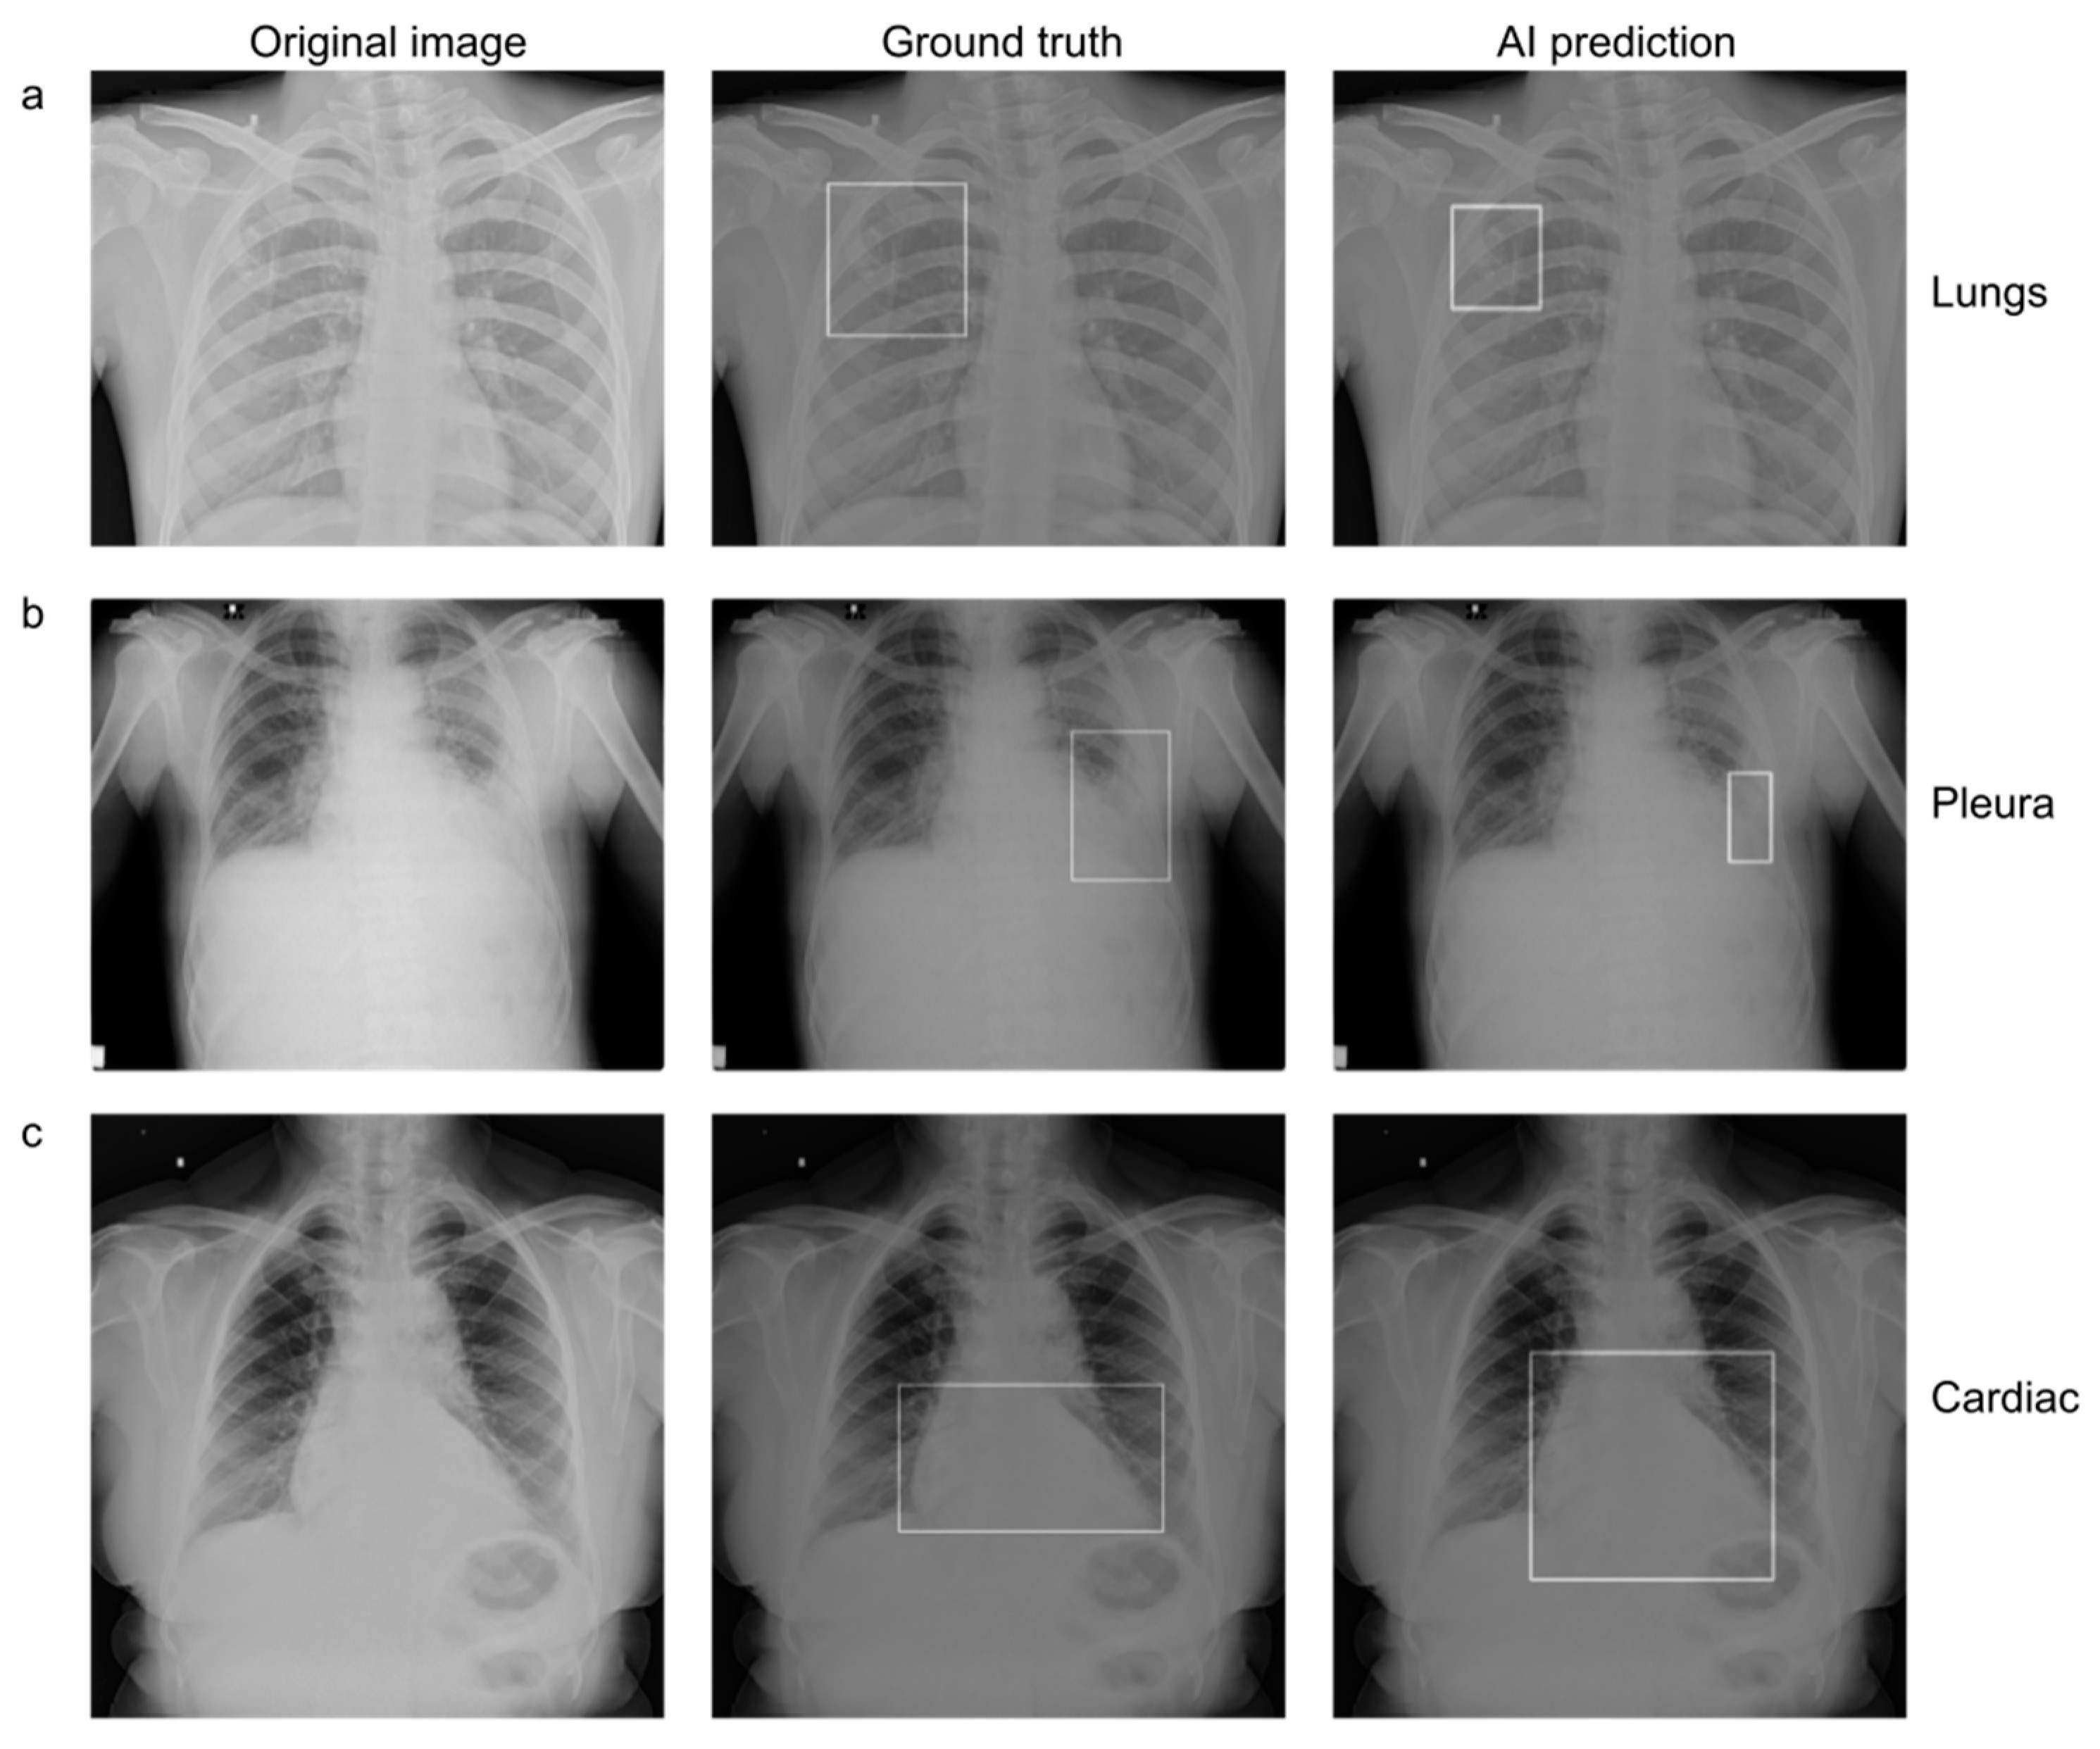

2.2. Establishing Ground Truth

2.3. AI Model

3.2. Standalone Performance of the AI Model